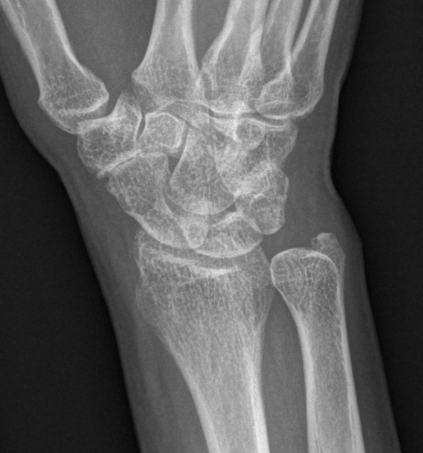

Isolated STT osteoarthritis

OA of the scapho-trapezium-trapezoidal (STT) joints

Third most common wrist osteoarthritis after CMC OA and SLAC wrist

- associated with CMC OA in 60% of cases

- often bilateral